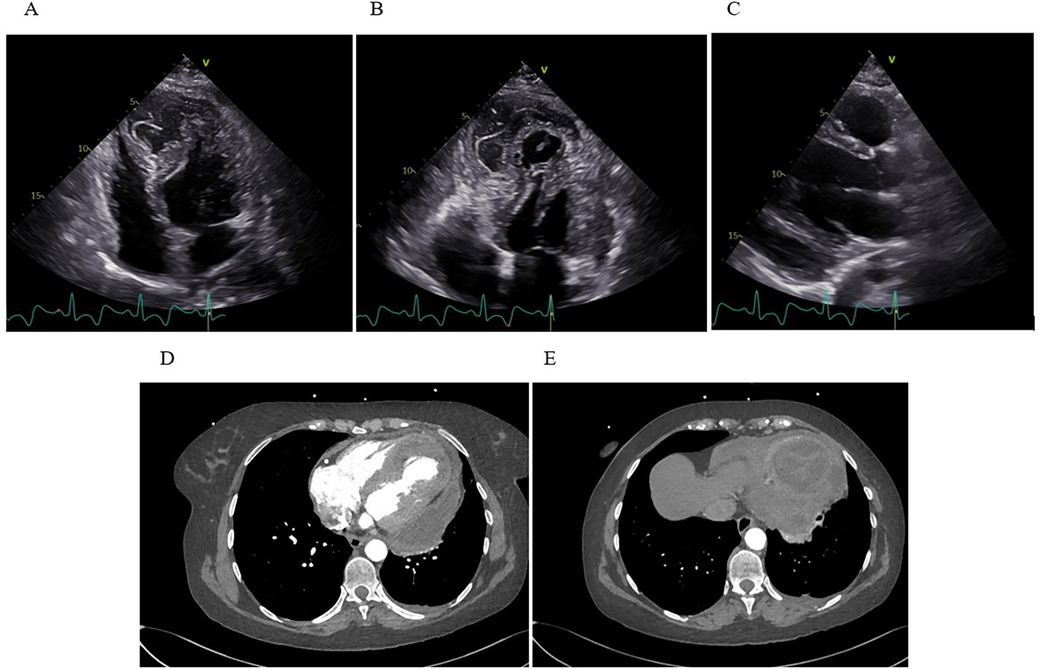

Initially diagnosed as stress-induced myocardial dysfunction, she was transferred back to a secondary hospital for further observation. Shortly thereafter, she became febrile (temperature up to 38.2°C) and was treated with oral penicillin for streptococcal pharyngitis. Despite therapy, inflammatory markers (CRP 192 mg/L) remained high, and troponin rose to 4,584 ng/L. TTE on September 16 demonstrated a moderately dilated LV [end-diastolic diameter (EDD) 60 mm], dyskinesia of the apical segments of the LV, mild pericardial effusion, and suspicious “layering” in the LV wall consistent with intramyocardial bleed or pseudoaneurysm (Figure 1).

Figure 1

Transthoracic echocardiography. (A,B) Apical four-chamber view shows apical and inferoseptal myocardial thickening with a large, echolucent, spindle-shaped intramyocardial cavity, without evident communication to cardiac chambers or pericardial space. (C) Contrast echocardiography demonstrates no flow from the ventricular cavity into the lesion.

Clinical deterioration and surgical decision

By day 30, the patient again became febrile with rise in inflammatory markers (CRP spiking to 339 mg/L, procalcitonin up to 0.71 µg/L). This prompted a heightened concern for infective hematoma or pericarditis. TTE revealed newly present pericardial effusion along the lateral and inferior wall of the LV with a fluid layer of up to 22 mm. The intramural fluid collection also looked more heterogeneous and potentially communicated with the pericardial space (Figure 3).

Figure 3

Transthoracic echocardiography and computed tomography. (A) Apical four-chamber view showing extensive IDH with marked apical dyskinesia. (B) Apical thrombus formation visualized as an echogenic mass at the ventricular apex. (C) The parasternal long-axis view reveals a moderate, new pericardial effusion along the inferolateral wall of the LV. (D) Axial CT demonstrates a multiloculated, heterogeneous fluid collection within the inferoapical myocardium, with clear communication to a large pericardial effusion along the lateral and posterior walls of the LV. (E) A separate axial CT slice shows a clearly defined, round, intramyocardial lesion.

Later that day, the patient underwent additional imaging, including a CT scan of the chest, which showed a large, multi-chambered fluid collection in the inferoapical myocardium, measuring about 65 × 55 × 33 mm, communicating widely through a 20 mm channel with a separate large fluid pocket of approximately 55 × 25 × 100 mm running from the apex along the lateral wall up to the cardiac base (Figure 3). The concern was that the previously noted intramural hematoma had partially liquefied and extended into the pericardial space. The possibility of infection or an abscess could not be fully excluded.